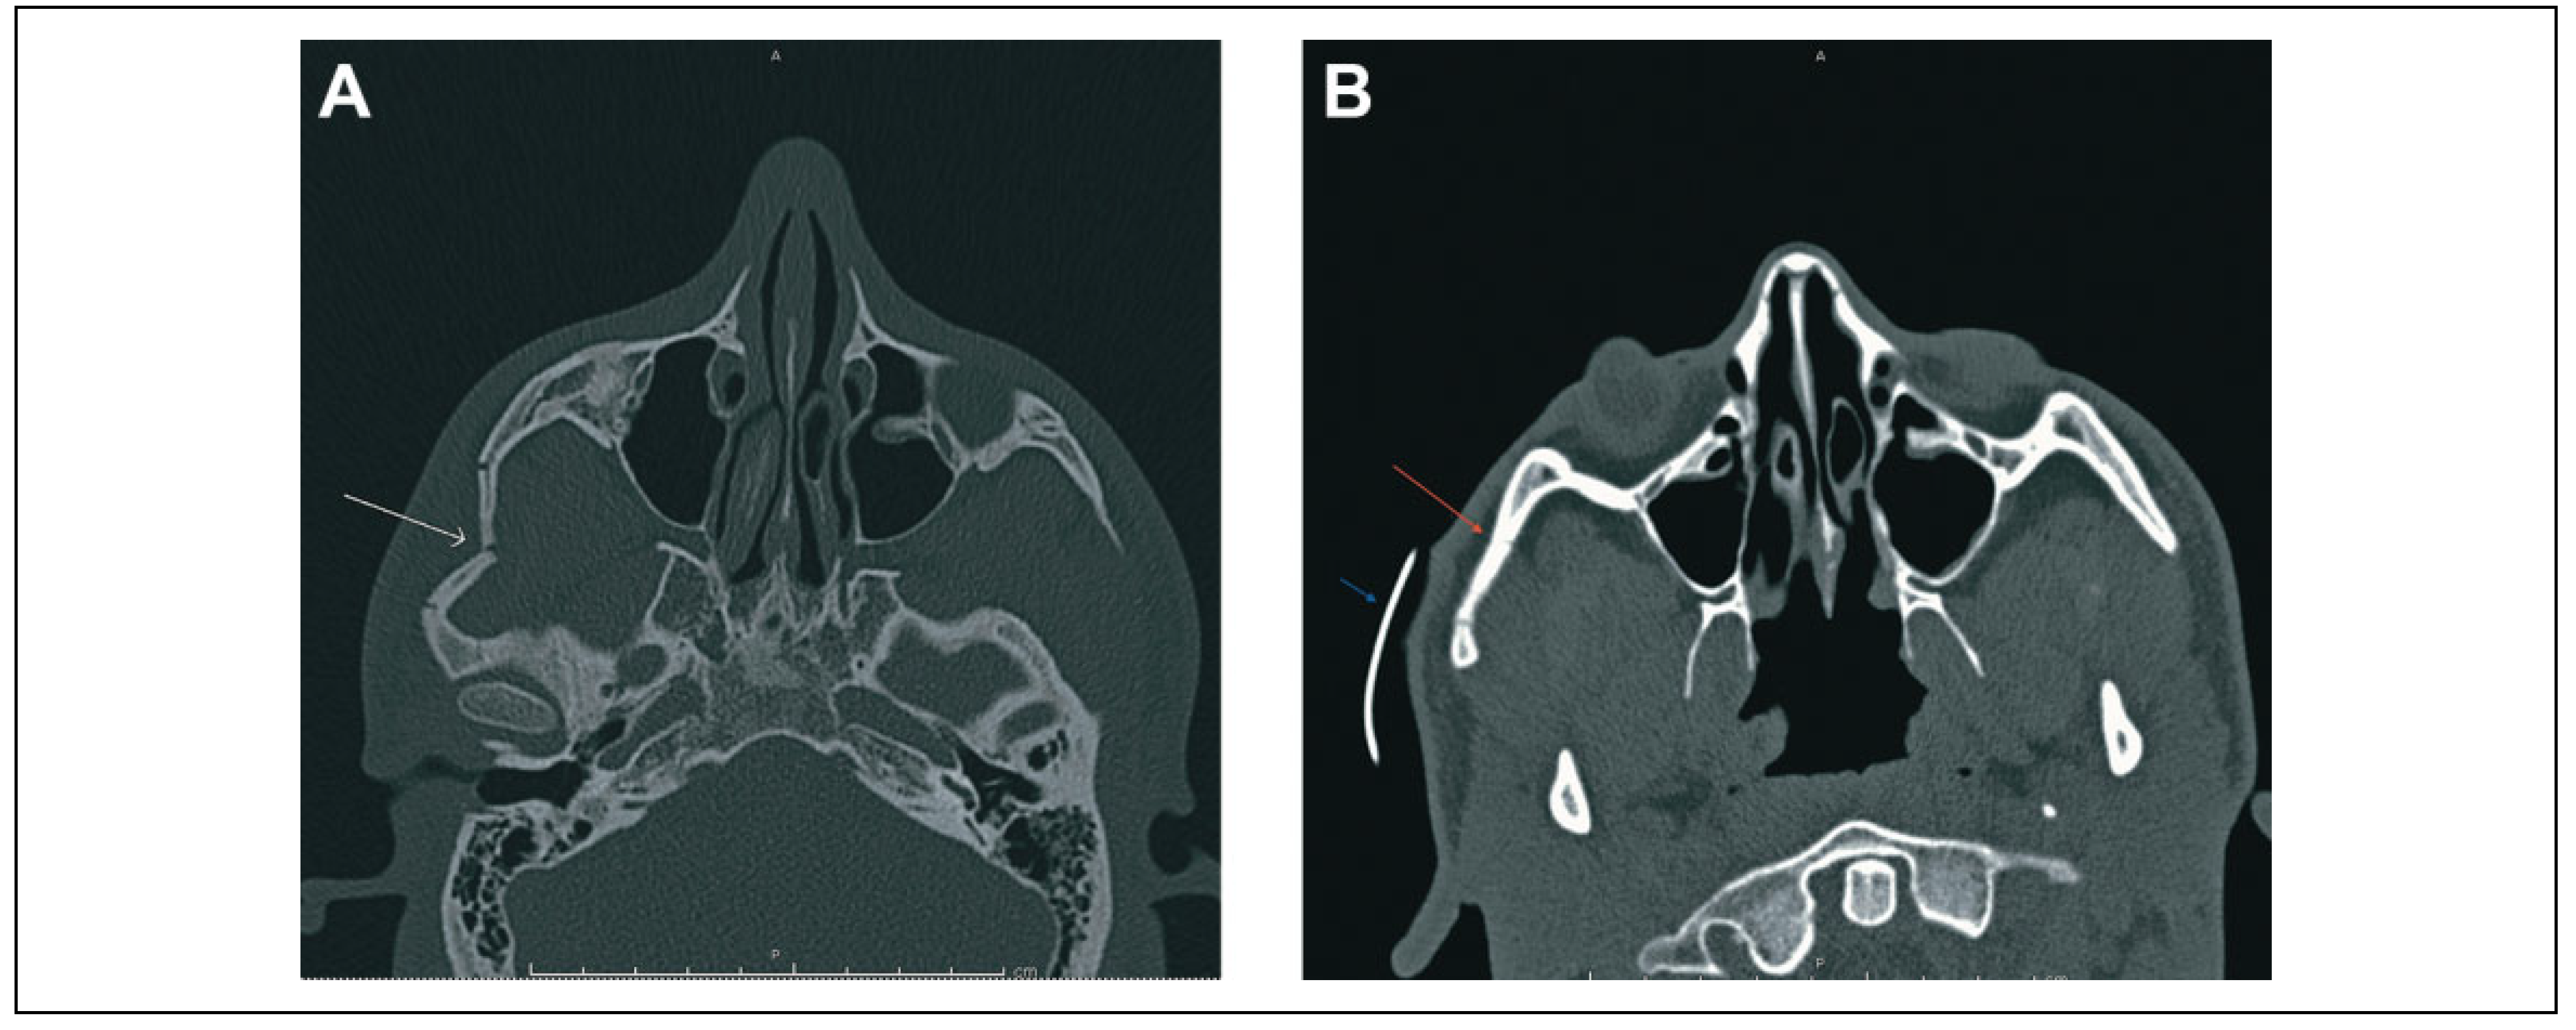

A 21-year-old African American male who sustained a right-sided, isolated zygomatic arch fracture as a result of an automobile versus pedestrian accident. On physical examination, he had a clear step-off deformity palpated over the right malar eminence, trismus with interincisor distance of 1.5 fingerbreadths, and paresthesia in the V2 distribution. The right zygomatic arch was noted to be severely comminuted and displaced on CT maxillofacial scan prior to repair (Figure 4A). Following open reduction external fixation as described earlier, a repeat maxillofacial CT scan was performed, which showed proper reduction of the right zygomatic arch (red arrow) prior to removal of the external fixation splint in proper position 3 weeks later (Figure 4B). At follow-up, the patient had marked improvement in malar contour appreciated on oblique (Figure 5A) and frontal (Figure 5B) views. The patient had minimal skin changes overlying the splinted area, and there was complete resolution of his paresthesia and trismus.

Figure 4. Preoperative (A) and postoperative (B) appearance of the right zygomatic arch on computed tomography scans (white arrow—right zygomatic arch fracture prior to treatment; red arrow—right zygomatic arch status-post open reduction external fixation; and blue arrow—external splint in place overlying the right zygoma).